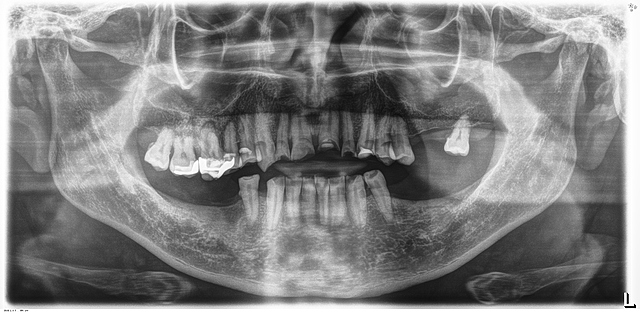

• Análisis radiográfico, Modelos de estudio y análisis intraorales.

Análisis radiográfico, Modelos de estudio y análisis intraorales.

Se realizó la elaboración de los materiales de estudio para poder crear un diagnostico adecuado sobre el tratamiento a realizar.

Disminución de la dimensión vertical.

Recesión gingival y perdida de cortical vertical por extrusión: 1.6

Ausencia: 2.6, 2.7, 3.5, 3.6, 3.7, 3.8, 4.4, 4.6, 4.7 y 4.8.

Caries: 2.8, 2.5, 2.4, 1.5 y 1.8

D. pulpar (1.4): necrosis pulpar.

D. periapical: periodontitis apical crónica.

D. pulpar (1.2, 2.1, 2.2, 2.3): pulpa sana, endodoncia por fines protésicos.

D. periapical: periápice sano.

F. desgaste: 1.3, 1.2, 1.1, 2.1, 2.2, 2.3, 2.4, 3.3, 3.2, 3.1, 4.1, 4.2, 4.3 y 4.5.

Amalgama: 1.7 y 1.6.